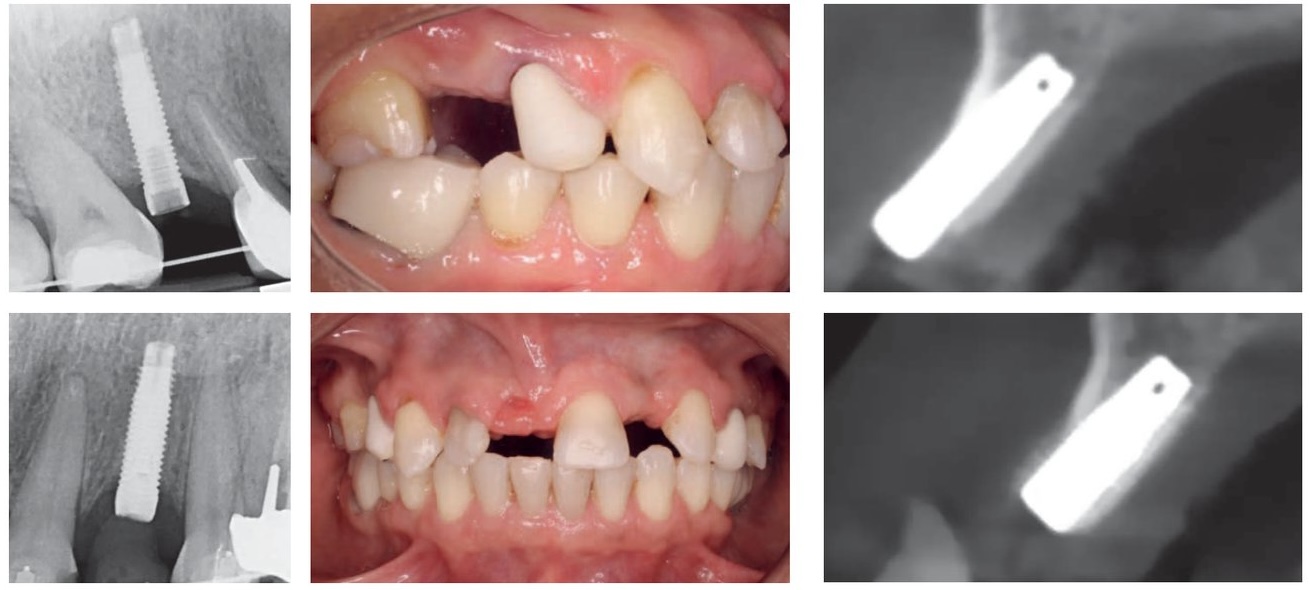

Réintervention — Implants atteints de péri-implantite dans une réhabilitation globale

Dans ce cas de réintervention, la patiente, très exigeante sur le plan esthétique, souhaite avoir un plan d'occlusion symétrique, un alignement des collets et des dents plates.

Cette patiente est adressée par son praticien traitant pour un problème de péri-implantite qui évolue négativement malgré une maintenance régulière et plusieurs tentatives de prise en charge. Les implants de 14 et 22 présentent des axes fortement vestibulés probablement associés à de légères déhiscences osseuses ce qui explique les décalages au niveau de ces collets ainsi que le grisé du métal qui transparait au niveau de ces sites. Le bilan radiographique montre l'importance des pertes osseuses au niveau des implants de la 12 de la 26 et de la 27. Ces trois implants présentent une suppuration au sondage.

Les implants de 12 26 et 27 sont déposés d'emblée en raison de la sévérité de leurs atteintes péri-implantaires. 14, 22 et 23 sont conservés et vont servir à mettre en place un bridge transitoire.

Il aura fallu près de 12 mois de traitement pour obtenir ce résultat qui n'a permis de conserver que deux des ancrages implantaires initiaux.